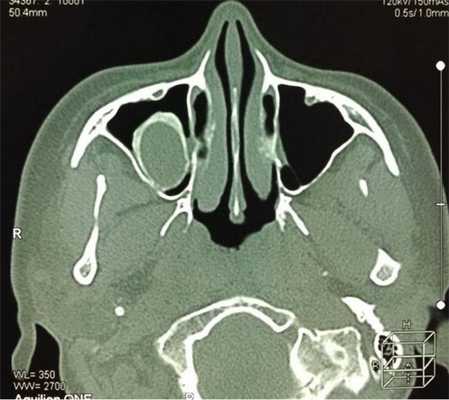

На снимке концентрическая воспалительная гипертрофия (указана стрелками) слизистой оболочки гайморовых пазух